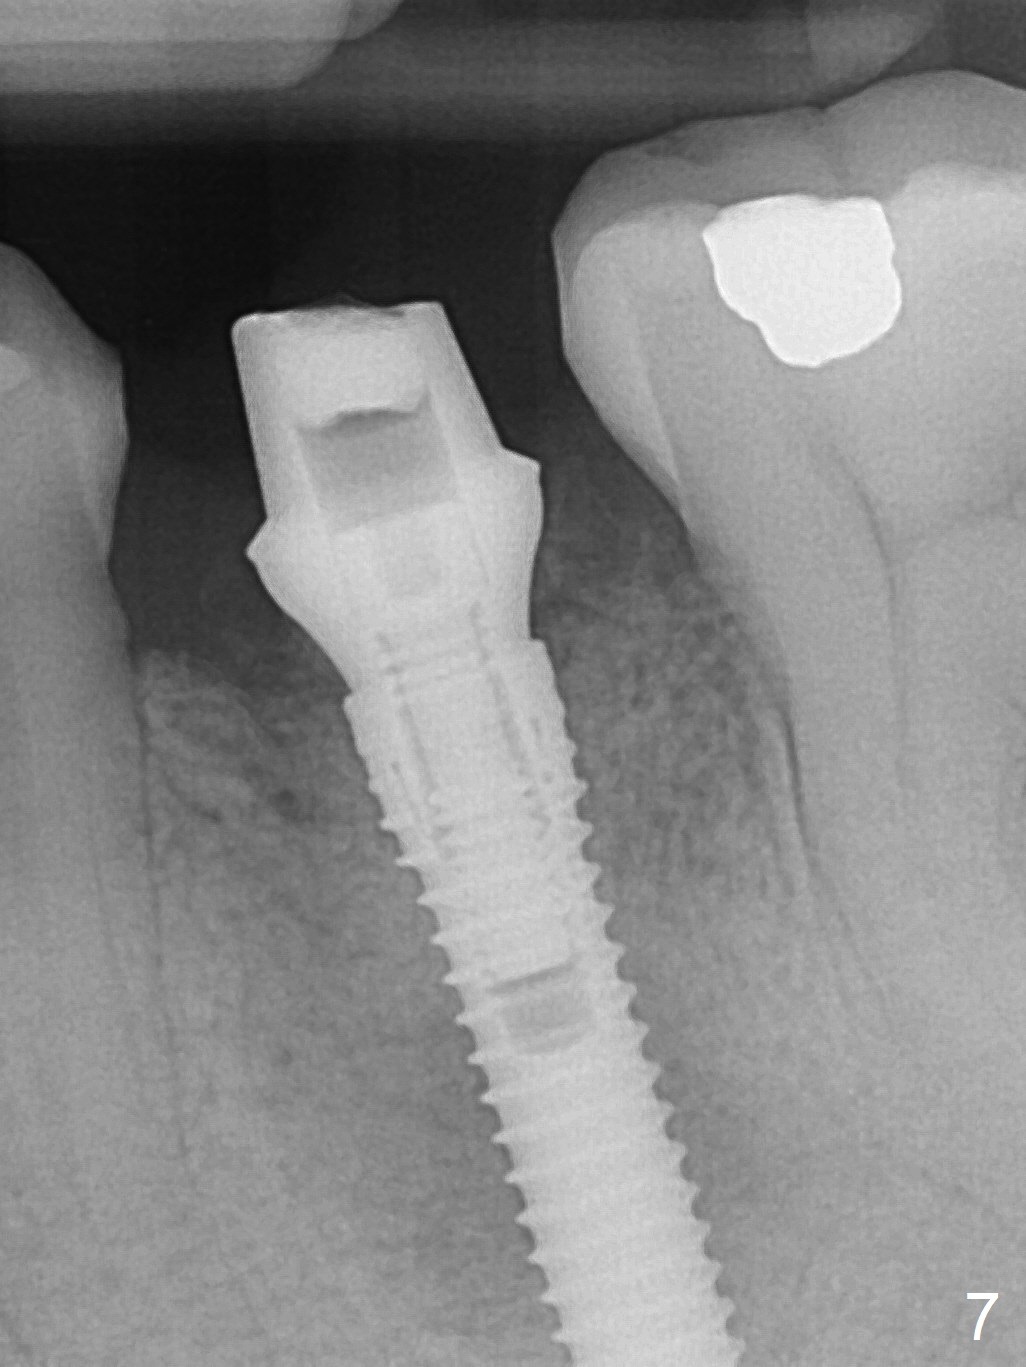

Extraction of the lower left 2nd premolar with vertical fracture (Fig.1,2 >) is easy because of peri-radicular radiolucency. The apical end of the osteotomy is not shown with a 2 mm pilot drill (Fig.3) or a 3.8x18 mm implant (Fig.4) in place. It appears that the implant is not placed deep enough. Following 3-4 more turns of the implant and placement of a 5.5x4(3) mm abutment (Fig.5 A), allograft is placed (*). A postop panoramic X-ray is taken (Fig.6); the osteotomy could have been deepened to reduce the possibility of periimplantitis. Retrospectively, the panoramic X-ray should be taken after use of the pilot drill. The bone around the implant appears to have regenerated 4 months postop (Fig.7,8). Bone density appears to continue increasing 9 months postop (i.e., 4.5 months post cementation, Fig.9). Bone loss is minimal 2 years post cementation (Fig.10).